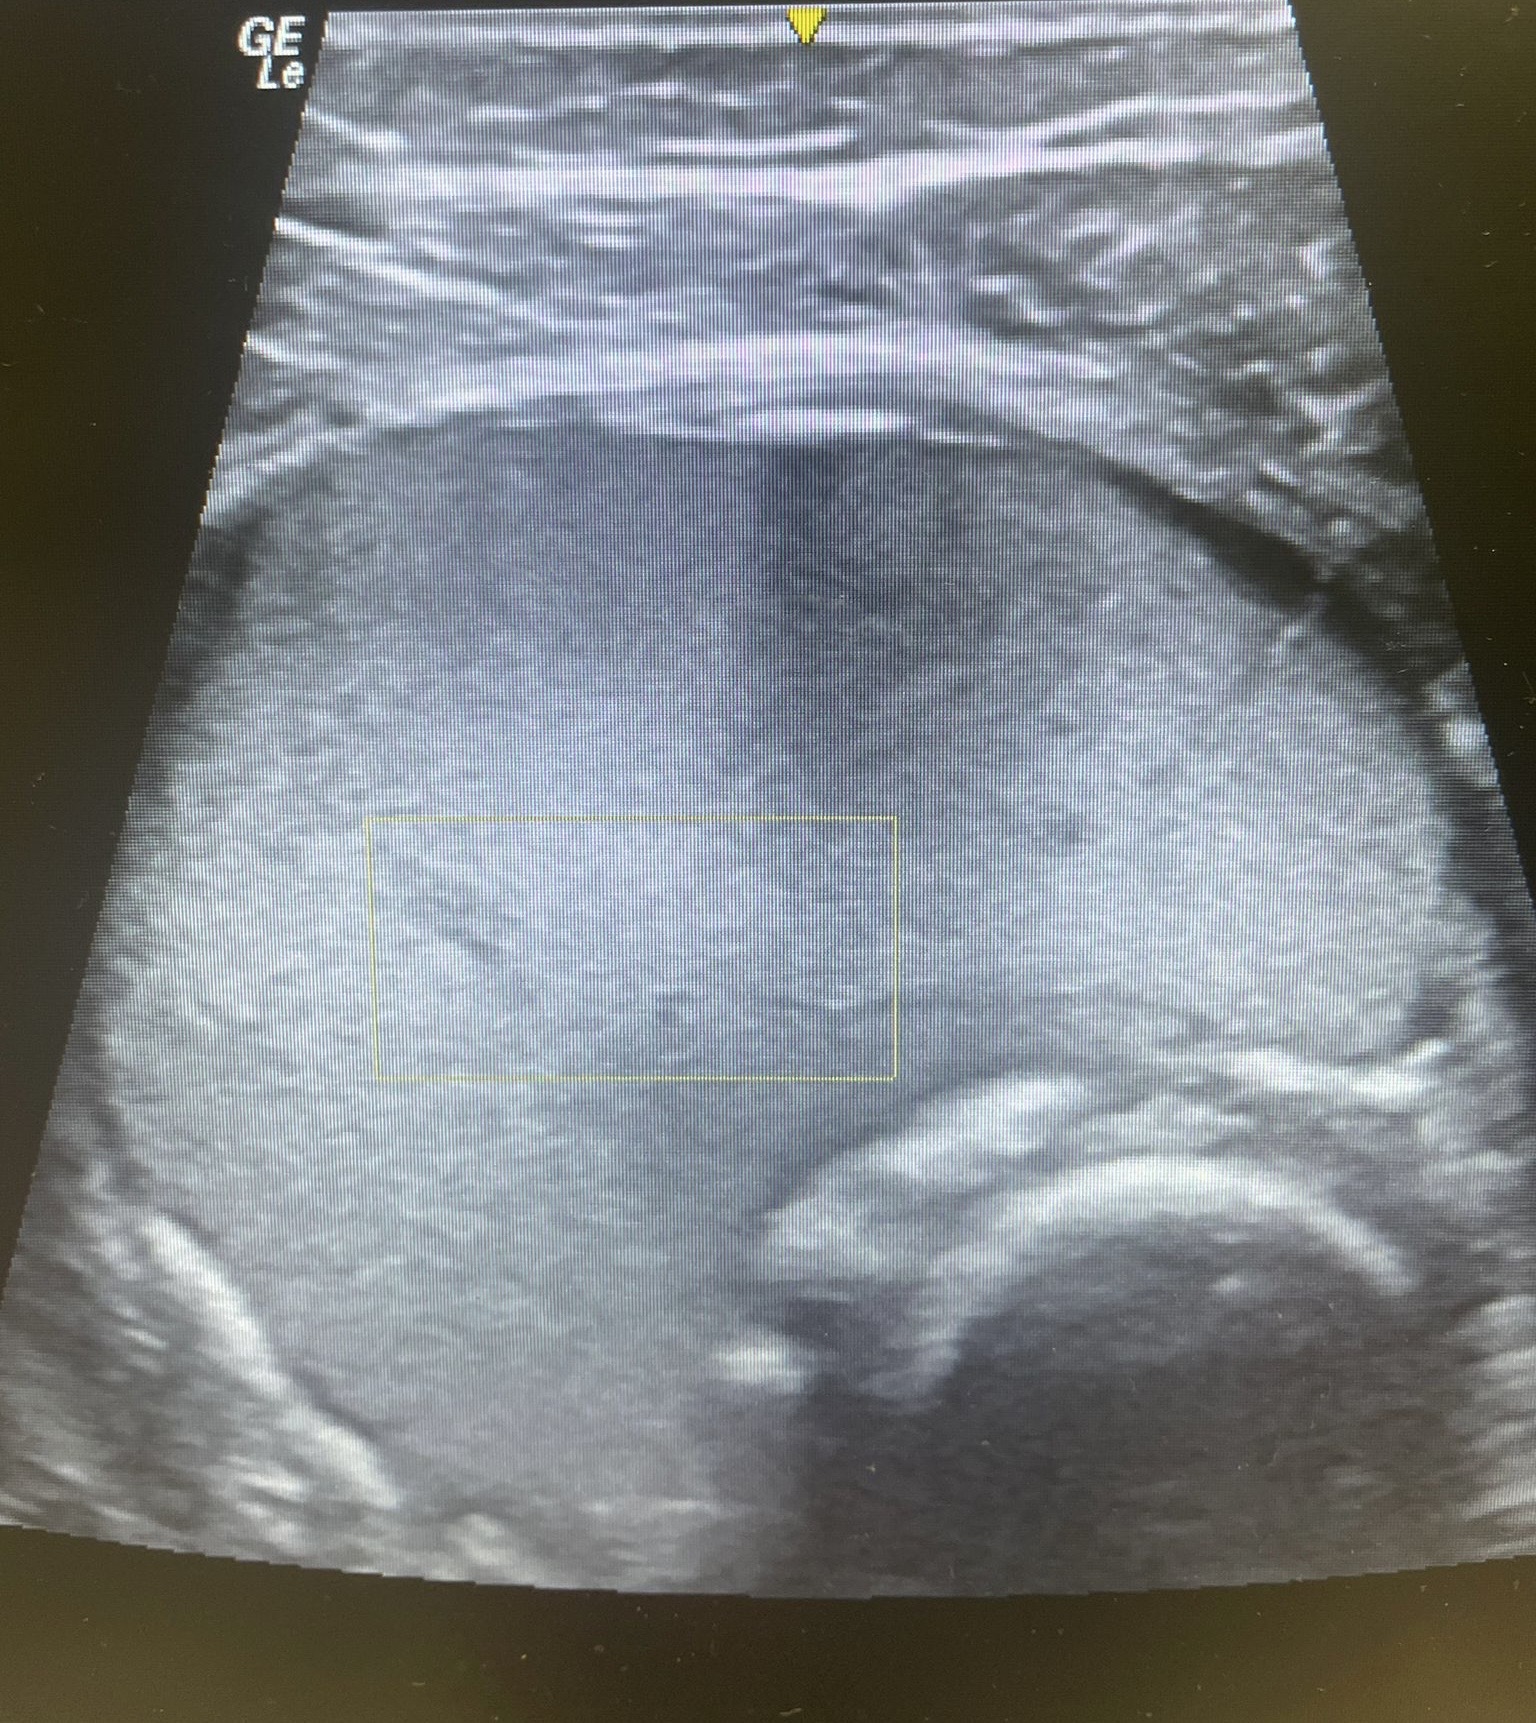

Hematoma no encapsulado de 5 x 9 cm en vasto intermedio, sin captación de doppler color y con aparición en bordes externos de calcificaciones con sombra acústica posterior.